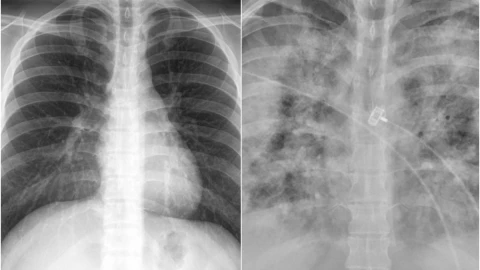

Faheem Younus, jefe del departamento de enfermedades infecciosas de la Universidad de Maryland, realizó una comparación con radiografías de pulmones de las personas no vacunadas contra las que sí se inyectaron contra el Covid-19.

En las imágenes que compartió en su cuenta de Twitter, Faheem Younus explicó que con la vacuna de Covid-19 se puede contraer la enfermedad, sin embargo, esta es generalmente leve, en comparación de las personas no vacunadas, que incluso llegan a la Unidad de Cuidados Intensivos (UCI).

Con la radiografía de los pulmones de personas no vacunadas y las que sí, el científico busca generar conciencia en la población para que se vacune, ya que puede ser la diferencia entre salvar la vida y no.

With Without

Vaccination Vaccination pic.twitter.com/GIcb5mJQz9